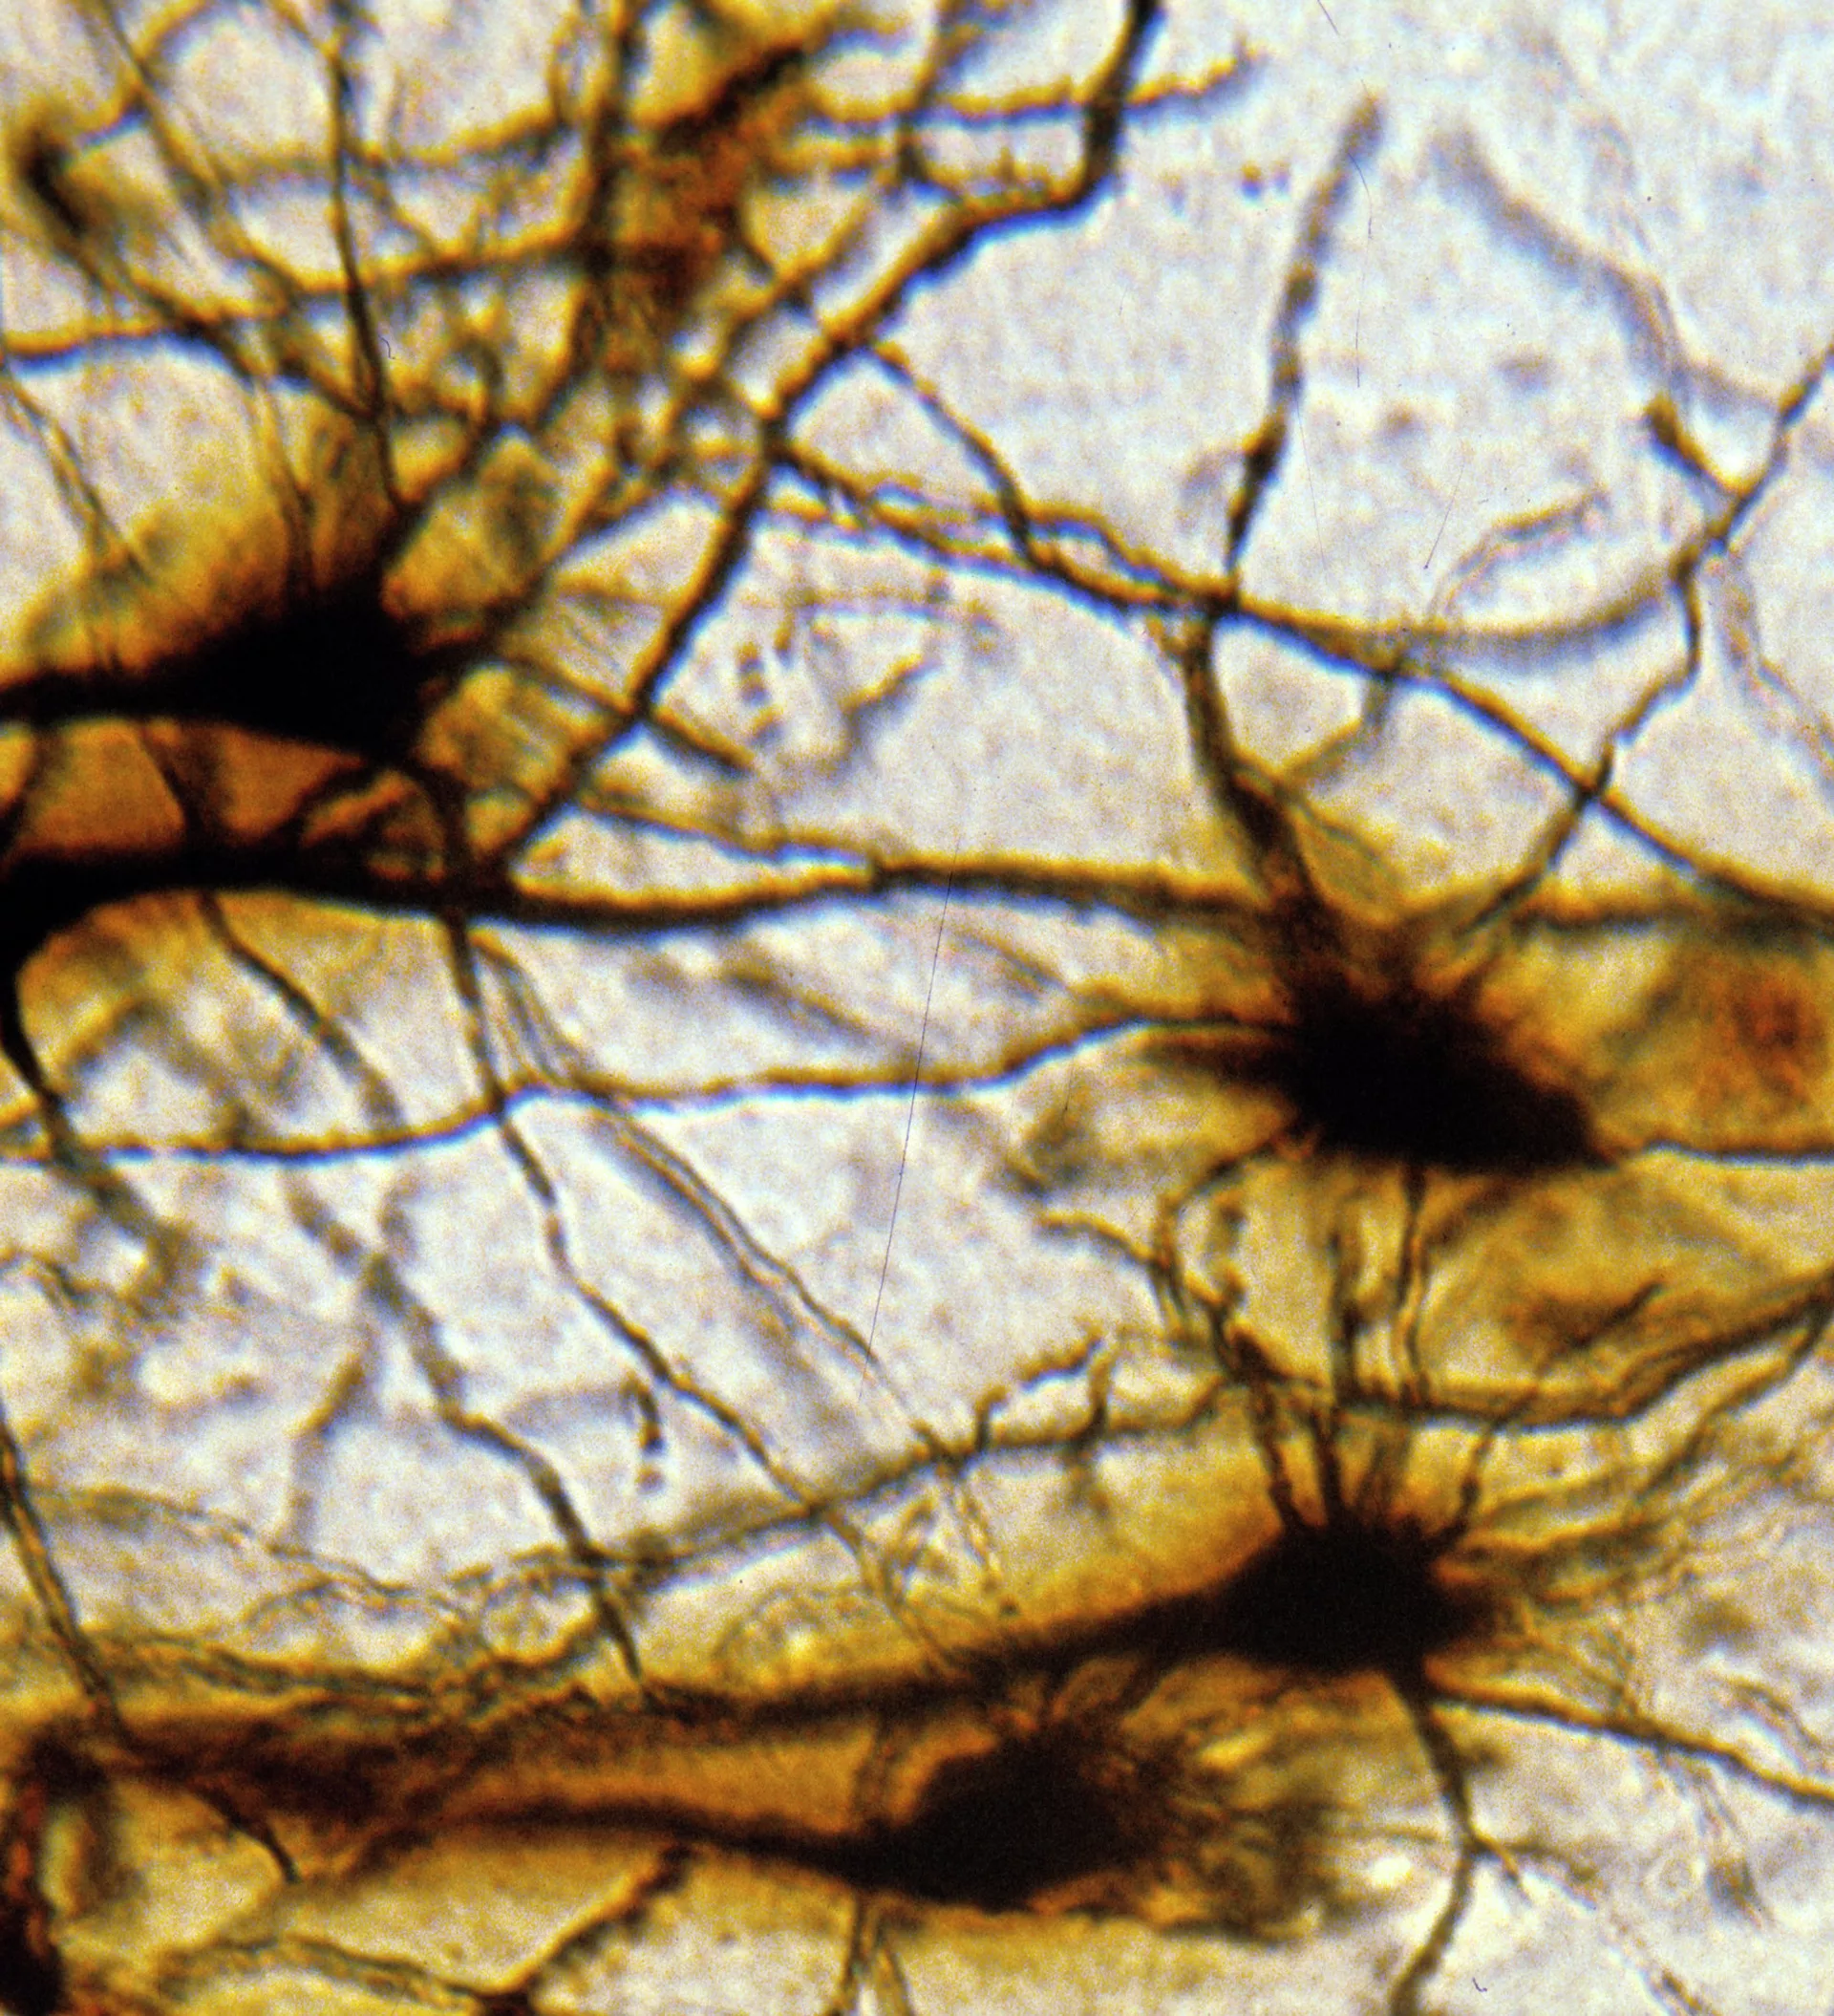

Внешний вид нейроинтерфеса, созданного американскими учеными, напоминает электроэнцефалографический головной убор. Он считывает электроимпульсы серого вещества и отдает соответствующие команды кибернетическому протезу.

Принцип работы нейропротезов прост: надевшему их достаточно представить то действие рукой, которое он хотел бы совершить.